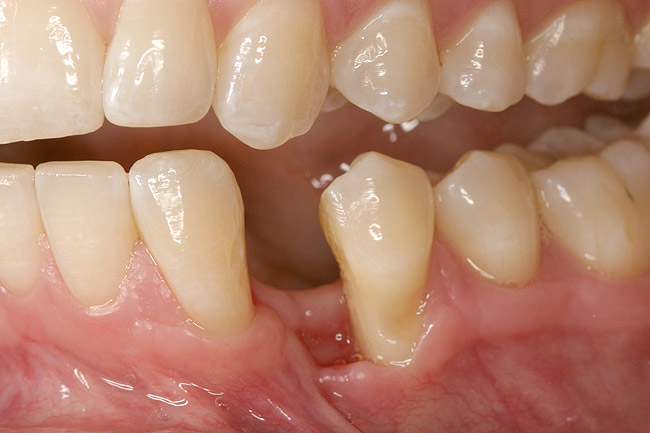

Figure 12  Right buccal view showing posterior occlusion established, canine guidance and proper space appropriation around peg lateral tooth No. 7, and intruded worn incisors.

Figure 12